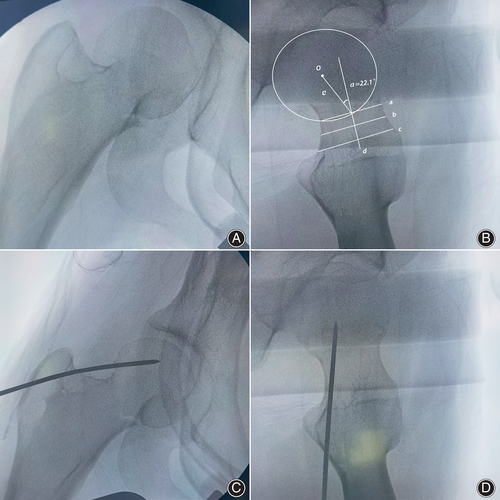

接下来,对残留的移位应用“内-外-内”经皮复位技术。在术中透视的帮助下,将带螺纹的斯氏针经皮钻入,通过股骨大粗隆上三分之一至股骨头。

在无股骨头后倾的外展嵌插型股骨颈骨折患者中,斯氏针的针尖将定位在股骨头中心;如果存在后倾,则斯氏针将从后方插入,向前倾斜至股骨头后部三分之一处。在透视下确认斯氏针的位置满意后,轻轻敲击针的末端,在透视监测下实现解剖复位。所有患者均通过经皮平行空心螺钉三角形配置固定。

其次,斯氏针的位置取决于是否存在后倾。在无股骨头后倾的外翻嵌插型股骨颈骨折患者中,斯氏针的针尖应定位在股骨头的中心;如果存在后倾,斯氏针应从后方插入,向前倾斜至股骨头后部三分之一处。

最后,斯氏针应在透视监测下轻轻敲击,以防止穿透股骨头。第四,在骨折复位理想后,斯氏针应保持作为临时固定和定位针,直到经皮平行空心螺钉插入完成。

这是首次描述“内-外-内”技术治疗伴或不伴后倾的外翻嵌插型股骨颈骨折的研究。该技术的局限性包括可能需要更多的放射线暴露,尤其是对经验不足的外科医生而言。此外,斯氏针的理想位置取决于外科医生的决策,特别是在存在后倾的情况下,缺乏客观标准来评估针尖的确切位置。